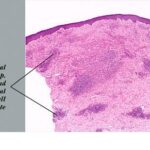

Common Tumorigenic Melanoma Including Nodular Melanoma Nodular melanoma by definition contains only tumorigenic vertical growth (sometimes associated with a precursor) and, because of this, has a poorer prognosis on the average than superficial spreading melanoma. However, when other risk factors such as thickness are controlled, the prognosis of nodular melanoma is not worse than that of other forms of melanoma . Nodular melanomas occur in slightly older patients than the common superficial spreading melanoma and are relatively more frequent in men . A nodular melanoma starts as an elevated, variably pigmented papule that increases in size quite rapidly to become a nodule and often undergoes ulceration. Certain rare primary dermal melanomas comprised of cytologically malignant melanocytes and lacking an in situ |

component may be considered also in this category . The ABCD criteria reviewed earlier do not apply to nodular melanomas, which often present clinically as quite small, symmetric, and well-circumscribed papules or nodules . These may be conspicuously pigmented, oligomelanotic, or even amelanotic. The tumorigenic nodule that may develop in nodular melanoma does not differ clinically or histologically from that which may occur in relation to a preexisting nontumorigenic melanoma. Indeed, nodular melanomas may represent examples of telescoped tumor progression in which the antecedent radial phase has been so short lived as to be unapparent . The clinical importance of the nodular subtype has been emphasized recently; these lesions are more likely to present at a biologically advanced stage despite a comparatively short clinical history . The mutation profile of nodular melanoma is closer to that of superficial spreading melanoma than to the other subtypes, in that BRAF or NRAS are commonly mutated . |

Histopathology of Nodular Melanoma and Common Vertical Growth Phase (Tumorigenic Melanoma) Architectural Features. In a typical tumorigenic melanoma, there is contiguous proliferation of neoplastic melanocytes in the dermis forming a tumor mass that is larger (usually much larger) than the largest nest in the |

Perhaps the best-known single criterion for melanoma is the upward pagetoid extension of tumor cells into the epidermis overlying the melanoma. However, this pagetoid melanocytosis or pagetoid spread is not specific for melanoma (152). Although in nodular melanoma, permeation of the epidermis with tumor cells may be absent or may be limited to that portion overlying the dermal tumor, lateral extension of melanoma cells in the epidermis and papillary dermis beyond the confines of the dermal tumor is seen in the adjacent nontumorigenic compartment of complex primary melanomas [SSM, LMM, acral-Ientiginous melanoma (ALM)]. This phenomenon greatly aids in histologic recognition of these tumors, and, conversely, the recognition of nodular melanomas, which lack this adjacent component, may be difficult. For this reason, nodular melanoma may be difficult or impossible to distinguish from a metastatic melanoma in the skin, and when such a tumor is amelanotic, the distinction from other cutaneous neoplasms may be impossible without immunohistochemistry. |